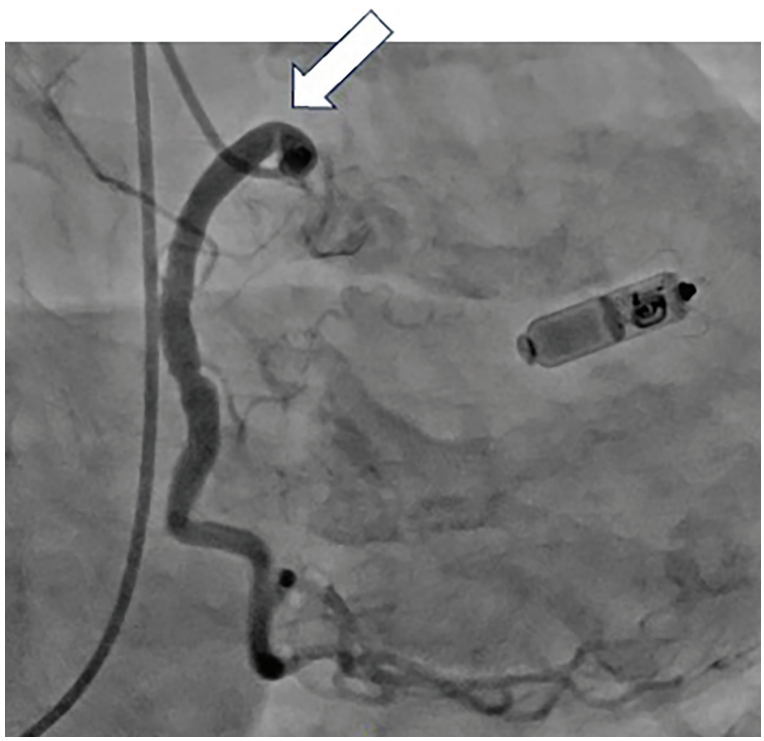

Kern-Fig3-CLD-MarchApril 2026_0.png

Figure 3. Angiogram of RCA in right anterior oblique (RAO) projection showing proximal narrowing of >70%.